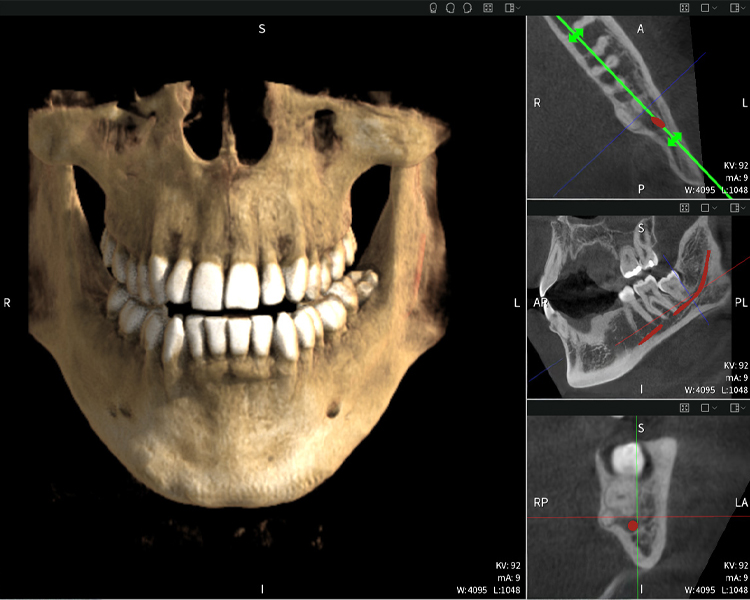

Nachstehend finden Sie einen Fall von Dr. med. dent. Oliver A. Centrella, in dem die CBCT-Aufnahmen mit Seethrough Max entscheidende Informationen zur komplexen Anatomie sowie zur kritischen Beziehung zwischen den Weisheitszähnen und dem Nervus alveolaris inferior lieferten. Bei diesem Fall besteht eine Indikation zur chirurgischen Entfernung der Weisheitszähne.

Abbildung a

- Oben links: Axiale Schnittansicht des linken Unterkiefers (Region 38) mit Darstellung des Nervus alveolaris inferior (rot) in unmittelbarer Nähe zu den Wurzeln des Zahns 38.

- Oben rechts: 3D-Rekonstruktion des gesamten Unterkiefers zur Orientierung. Der rot markierte Nervus alveolaris inferior verdeutlicht seine Lage im Kieferknochen.

- Unten links: Sagittale Ansicht des Unterkiefers (Region 38), die die enge räumliche Beziehung zwischen den Wurzeln und dem Nervenkanal verdeutlicht.

- Unten rechts: Koronale Ansicht des Unterkiefers (Region 38) entscheidend für die Beurteilung der räumlichen Lage der Wurzeln zum Nerven.